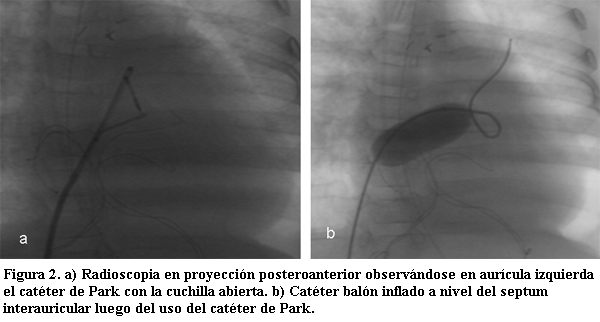

En caso de no existir pasaje a nivel del septum interauricular se puede realizar la perforación del mismo con una aguja especial (aguja de Brockenborough), o por radiofrecuencia; luego mediante un catéter “cuchilla” (catéter de Park), se hace un corte en el tabique interauricular para poder realizar la dilatación con balón; esta última es una alternativa para pacientes que requieran este procedimiento fuera del período neonatal (figuras 1 y 2).